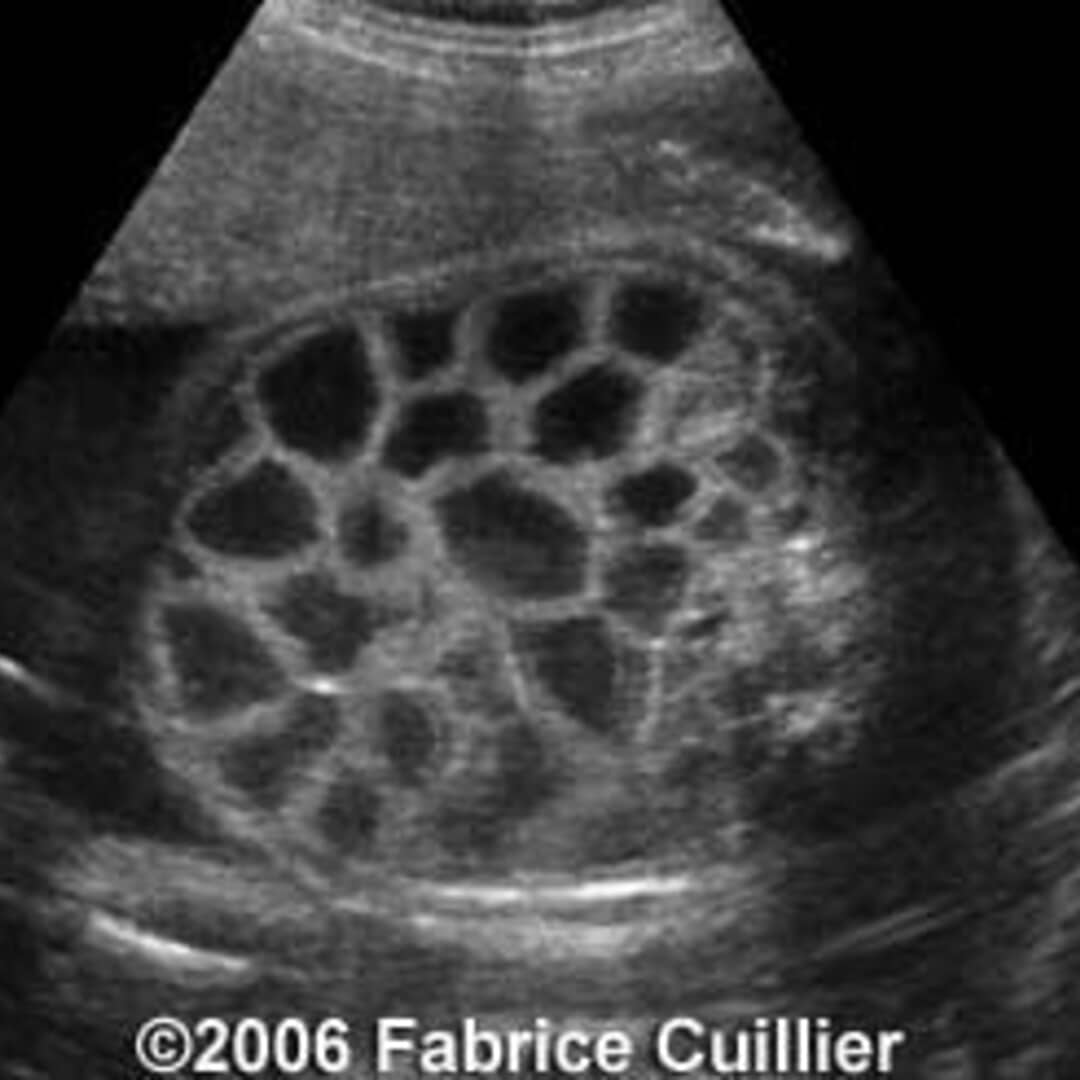

Congenital Chloride Diarrhea Accurate Prenatal Diagnosis Using Color Chloride Levels Diarrhea Your deficiencies and excesses will vary depending on the cause of the imbalance and come with their own set of consequences. what are the symptoms of hyperchloremia? Typically, hyperchloremia does not cause specific. This test is usually ordered as. chloride blood tests check to make sure you have appropriate levels of chloride in your blood to be healthy.. Chloride Levels Diarrhea.